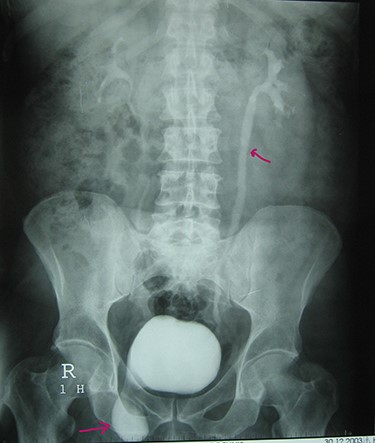

A 72-year-old man with a history of controlled diabetes and hypertension presented to our department with right inguinal swelling and intermittent lower urinary tract symptoms (LUTS) with pollakiuria, dysuria, prolonged micturition time and a sensation of a full bladder after micturition. He reported nausea, vomiting and right lower quadrant paint. The patient also reported having to manually compress the scrotum in order to empty the bladder. Physical examination revealed a slightly painful on palpation and reducible 6 cm right inguinal hernia extending into the right hemiscrotum. The body mass index of the patient was 31.4 kg/m2. His PSA was 4.3 ng/ml. On uroflowmetry, maximum flow rate (Qmax) was 13 ml/s and the voided volume was 180 cc. The uroflow curve was flat. The Bacteriological examination of urine was negative. Retrograde urethrocystography revealed right inguinal hernia containing a portion of the urinary bladder (Figs 1,2). He also had an intravenous urography in order to study the upper urinary tract and to have an idea of the renal function. This radiological exploration confirms the data of the retrograde urethrocystography and illustrates well the bladder hernia. However, a moderate left hydronephrosis with a nonobstructive pyelic calculus of 1.5 cm was observed on intravenous urography (Figs 3,4). Intraoperative findings revealed a direct right inguinal hernia with complete herniation of bladder into the scrotum. The bladder appeared healthy with no signs of injury and was restored to its normal anatomical position without resection. The hernia was repaired with a biologic mesh by the Lichtenstein technique. The patient had an uneventful postoperative course. Concerning his pyelic calculus problem, shock wave lithotripsy sessions were scheduled.

Retrograde urethrocystography: right inguinal hernia containing a portion of the urinary bladder.

Urethrocystography: no obstruction under the bladder in the per mictional image.